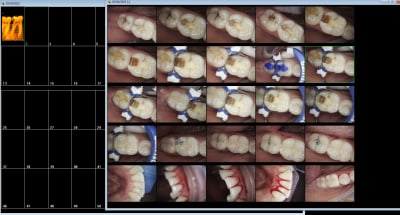

Cookie Consent byPrivacyPolicies.comVideo dentiste français , utilisation de silver diamine + - Eugenol

Video dentiste français , utilisation de silver diamine + verre ionomère